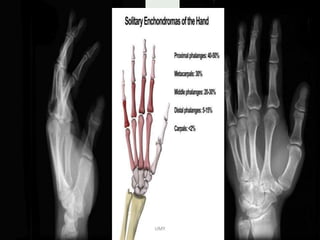

ENCHONDROMA

• small tubular bones of the hands

and feet : 50%

IMAGING

• X-ray & CT

Typically enchondromas are small 1 - 2cm lytic lesions with

non-aggressive features.

narrow zone of transition

sharply defined scalloped margins : may have mild

endosteal scalloping

expansion of the overlying cortex may be present but there

should not be cortical breakthrough unless fractured

Chondroid calcifications may be present : rings and arcs

calcification-STIPPLED/PUNCTATE/POPCORN

no periosteal rxn.

• The majority of enchondromas more frequently arise in

the metaphyseal region,.

A cartilaginous lesion in an epiphysis is more likely to be a

chondrosarcoma .